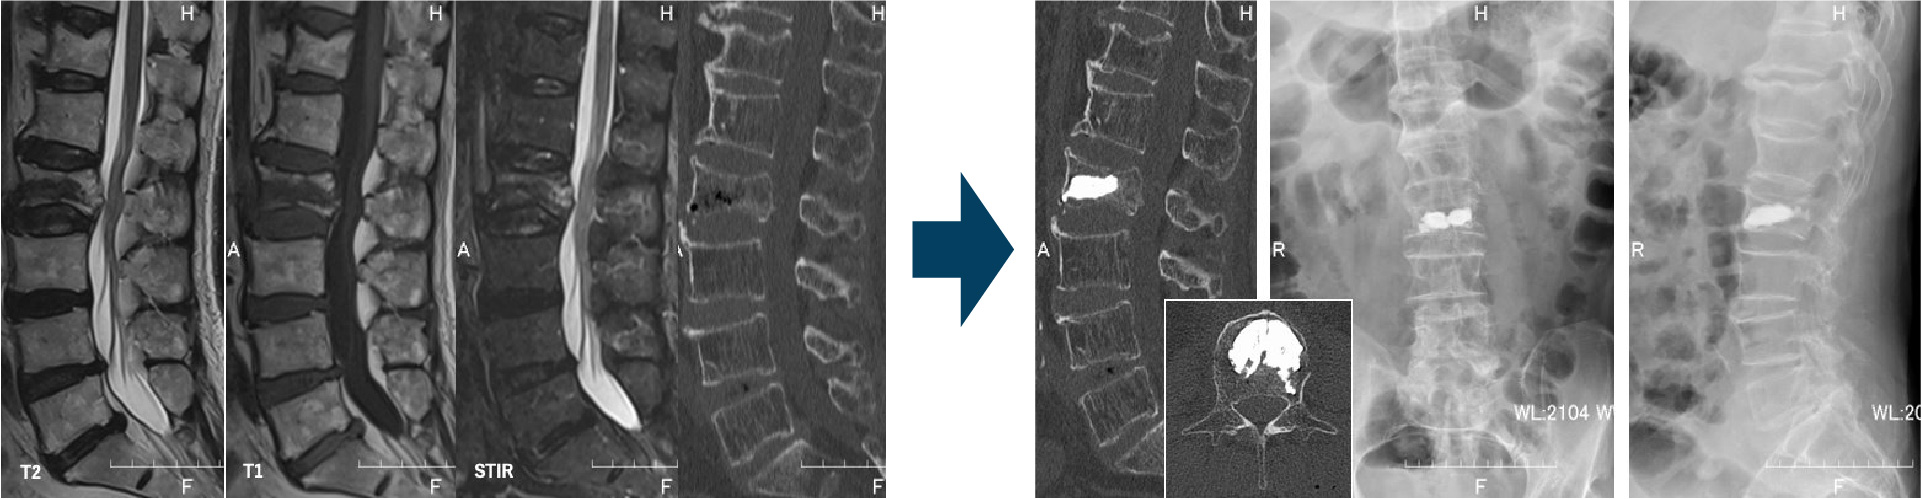

【第3腰椎圧迫骨折に対する経皮的椎体形成術+後方除圧固定術の実例】

椎体の変形が強く、一部の骨が椎体の後ろを通る神経を圧迫することで腰痛に加えて下肢痛を生じていました。折れた椎体自体にセメントを注入し、その上下の椎体にもボルトを打ち込み椎体の安定化をえました。さらに狭くなった神経の通り道を広げるために背中から背中から骨の一部を切除する除圧術を行っています。術後から腰痛及び下肢痛は軽減し、リハビリを開始することができています。